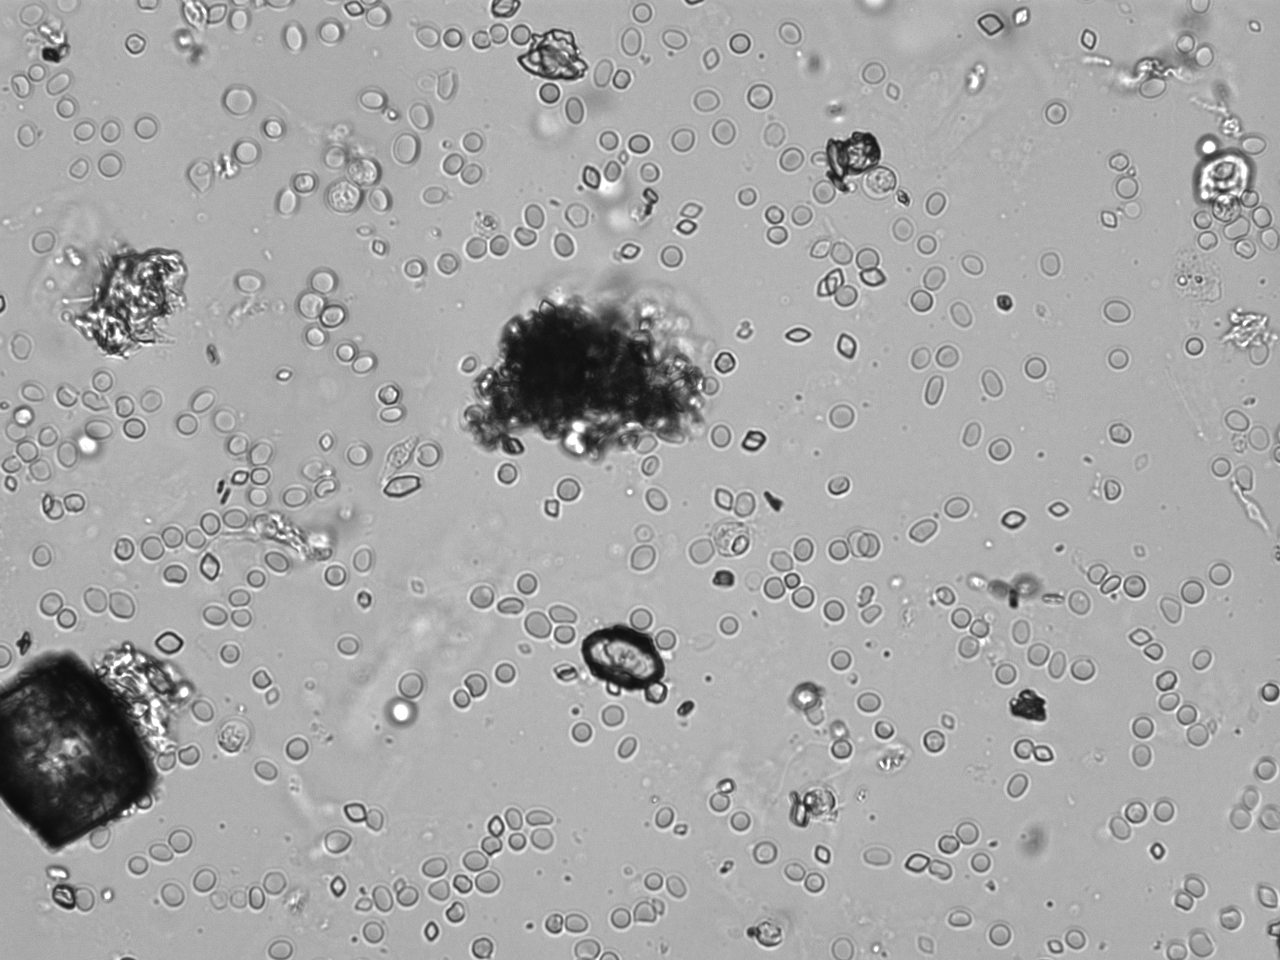

Urin-Feature: Harnskristalle_Rhomboid